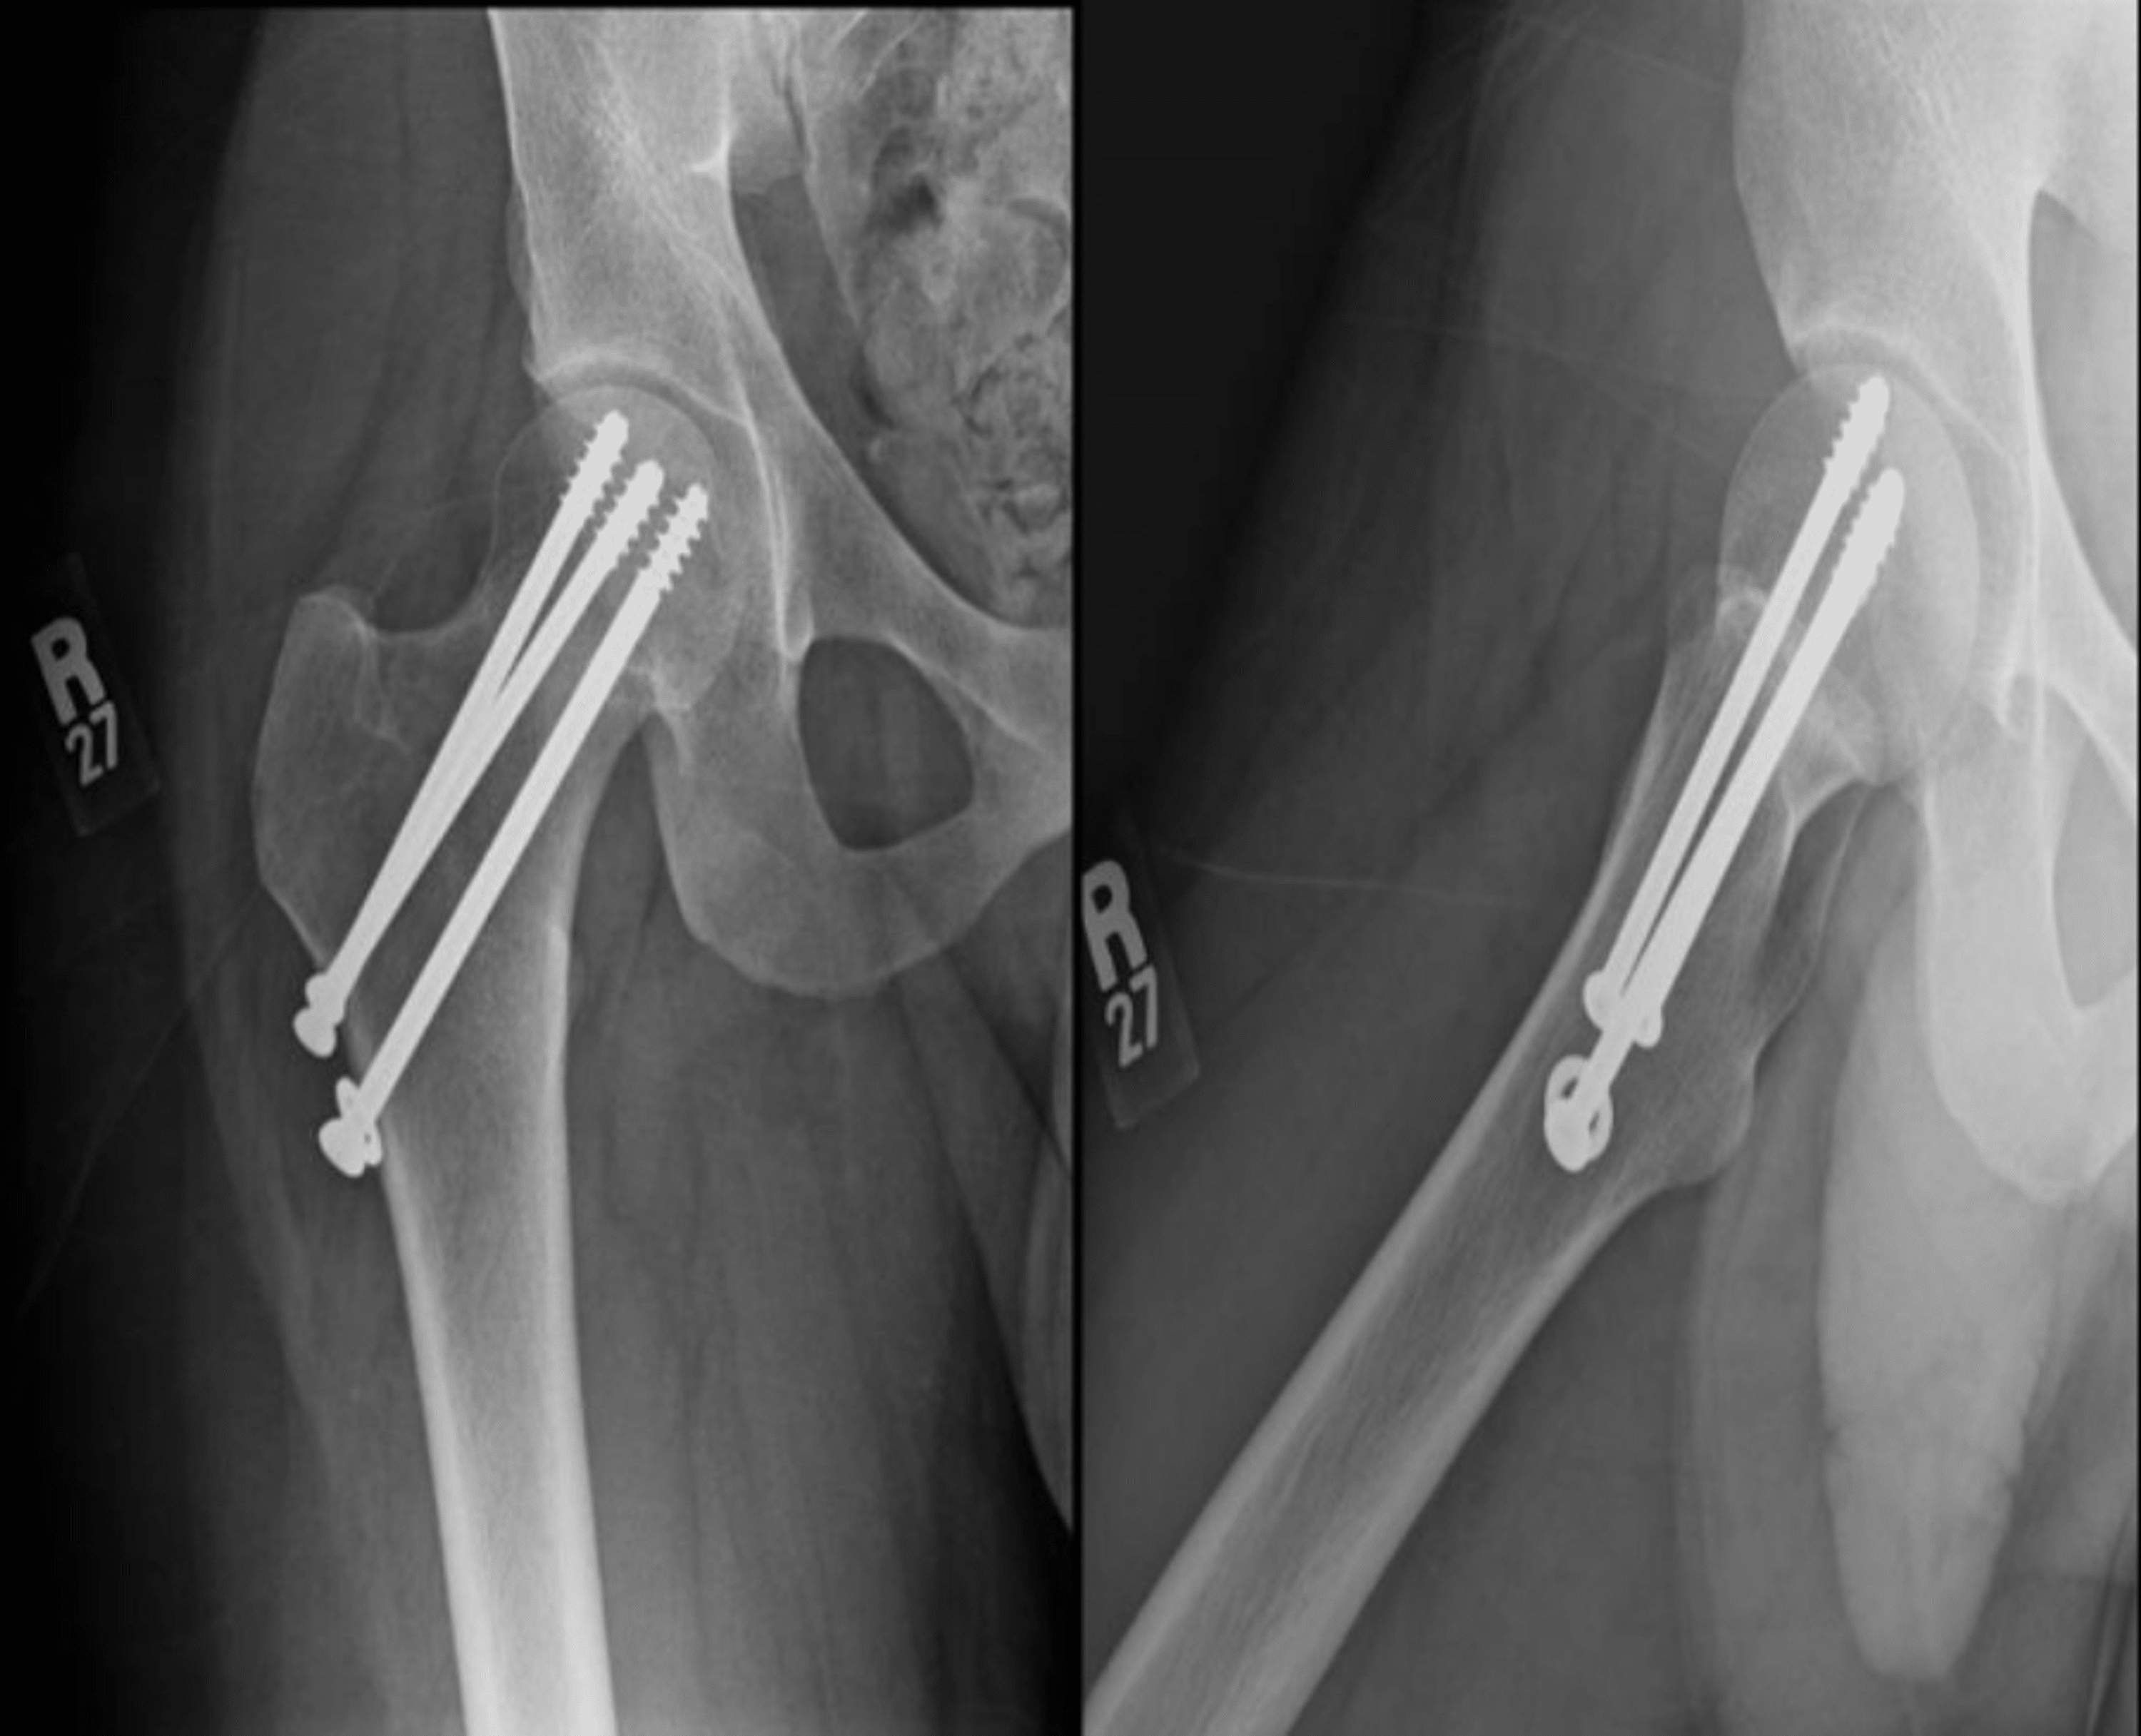

From www.cureus.com

Completely Displaced Femoral Neck Stress Fracture in a Young Male Stress Fracture Symptoms Femur They're caused by repetitive force, often from overuse — such as repeatedly jumping up and down or running long distances. Often a history of overuse. Femoral stress fractures occur in two different regions namely: Most common in young athletic individuals. Pain that starts and gets worse during physical activity. Overuse injury in which abnormal stresses are placed on cancellous bone. Stress Fracture Symptoms Femur.